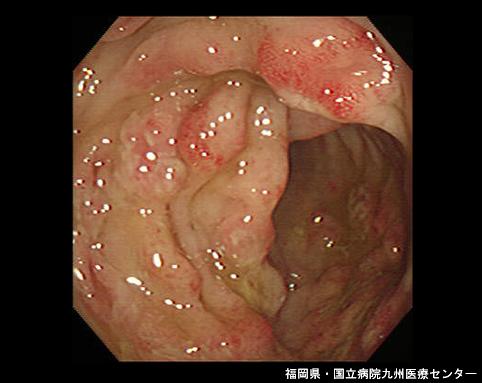

A case of amebiasis recognized in the rectum and sigmoid colon.

Fukuoka Pref., National Hospital Organization Kyushu Medical Center (Dr. 平賀)

Inflammatory or ulcerative disease / lesions/Amebiasis

Large intestine(Colon)/Rectum

Endoscopy